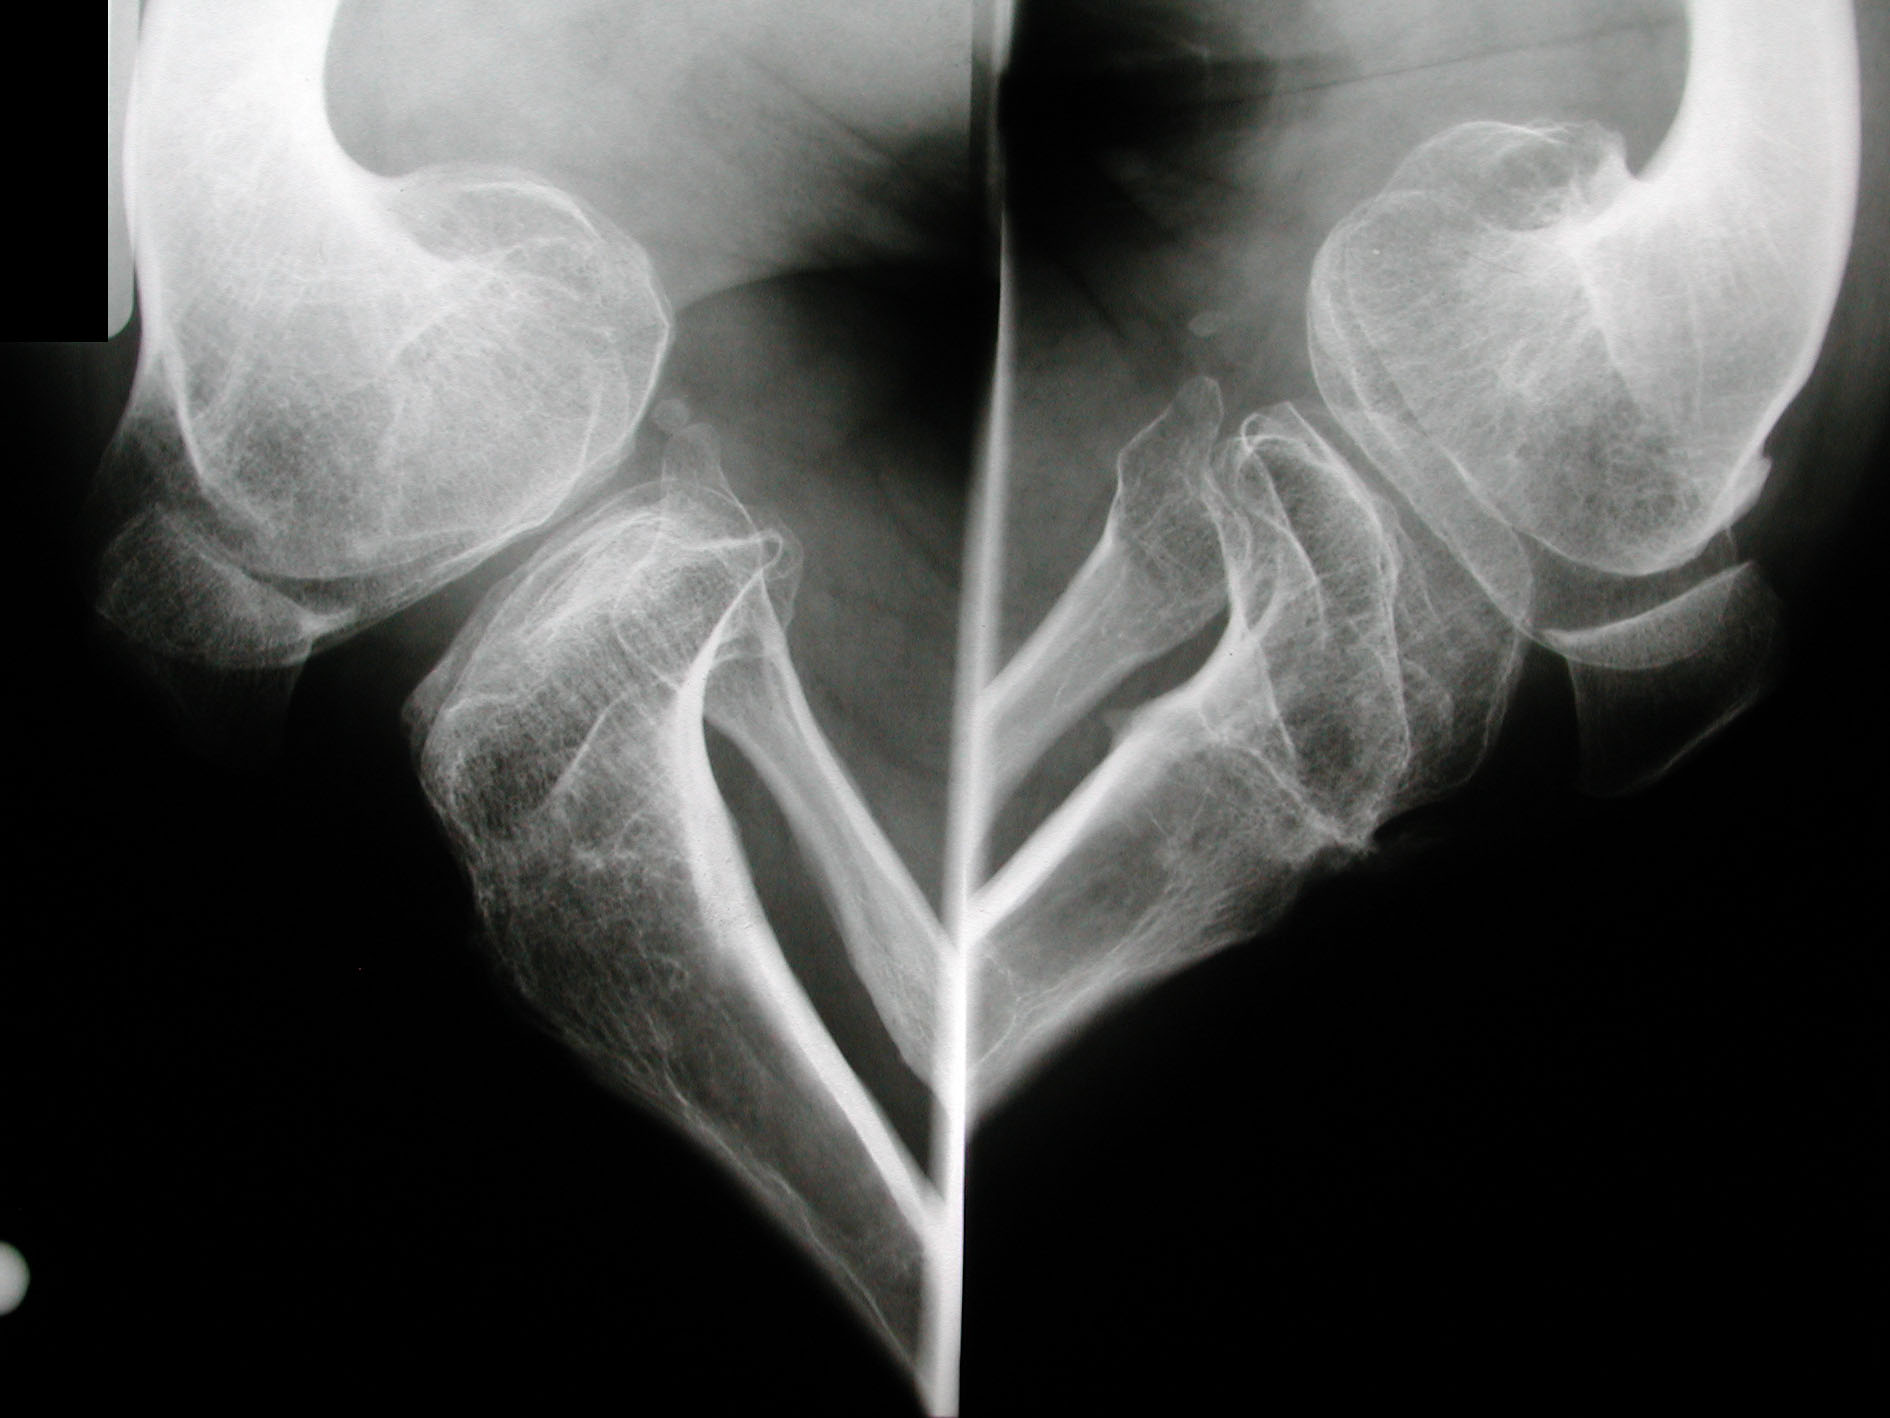

Seudoacondroplasia. [Pseudoachondroplasia]